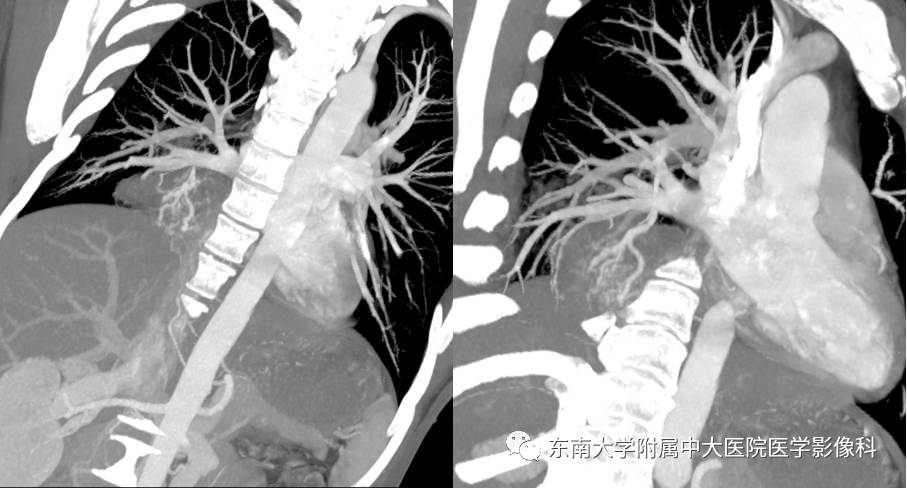

MIP

VR